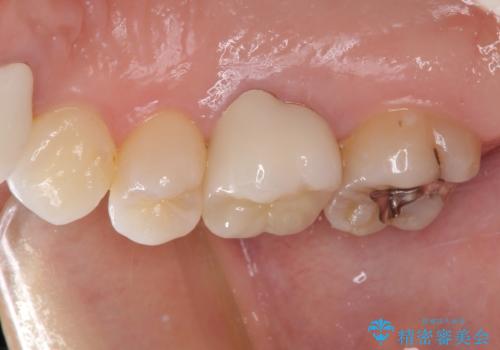

- 虫歯により神経を取り除いた前歯の変色が気になるとのことで来院された患者様です。

レントゲン写真より、歯根の炎症が認められなかったため、ファイバーコアによる土台築製後、オーダーメイドタイプのオールセラミッククラウンにて補綴することとしました。

他院で矯正治療をされていたそうですが、矯正治療前から変色は気になっており、歯並びが整ってからは、より気になるようになっていたそうです。